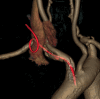

Neurological symptoms after parenteral nutrition

Keywords: intravenous/infusion nursing; parenteral/enteral feeding; stroke.